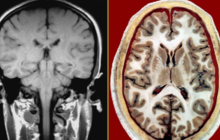

人体断层影像解剖学

课程代码:mk003336